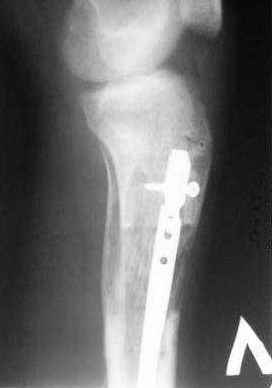

3,4 - через 4 недели наложен спице-стержневой аппарат, произведена остеотомия большеберцовой кости в верхней трети, раны зажили, проводилась дистракция в аппарате.

5, 6 - через 2,5 мес после травмы выполнен закрытый остеосинтез блокируемым штифтом.